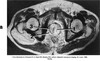

What pathology is seen here?

Polycystic Kidney Disease